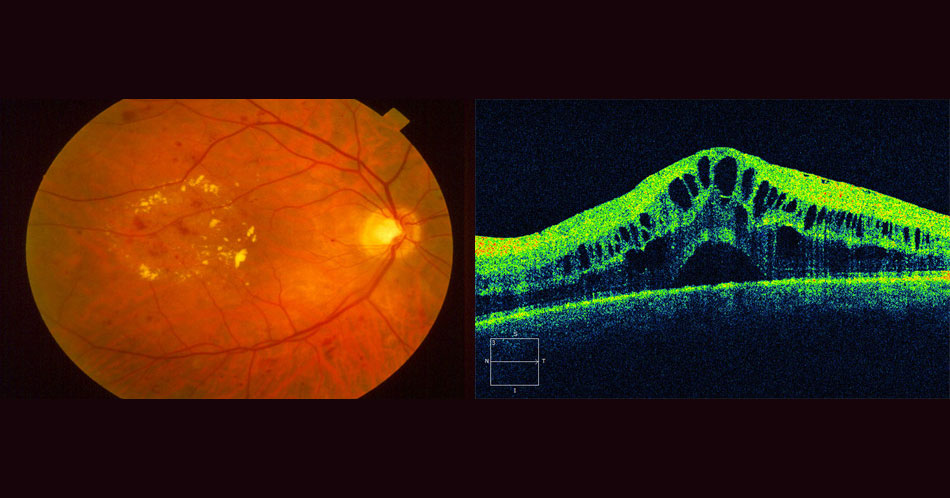

Диагностика зрения: Когерентная томография сетчатки